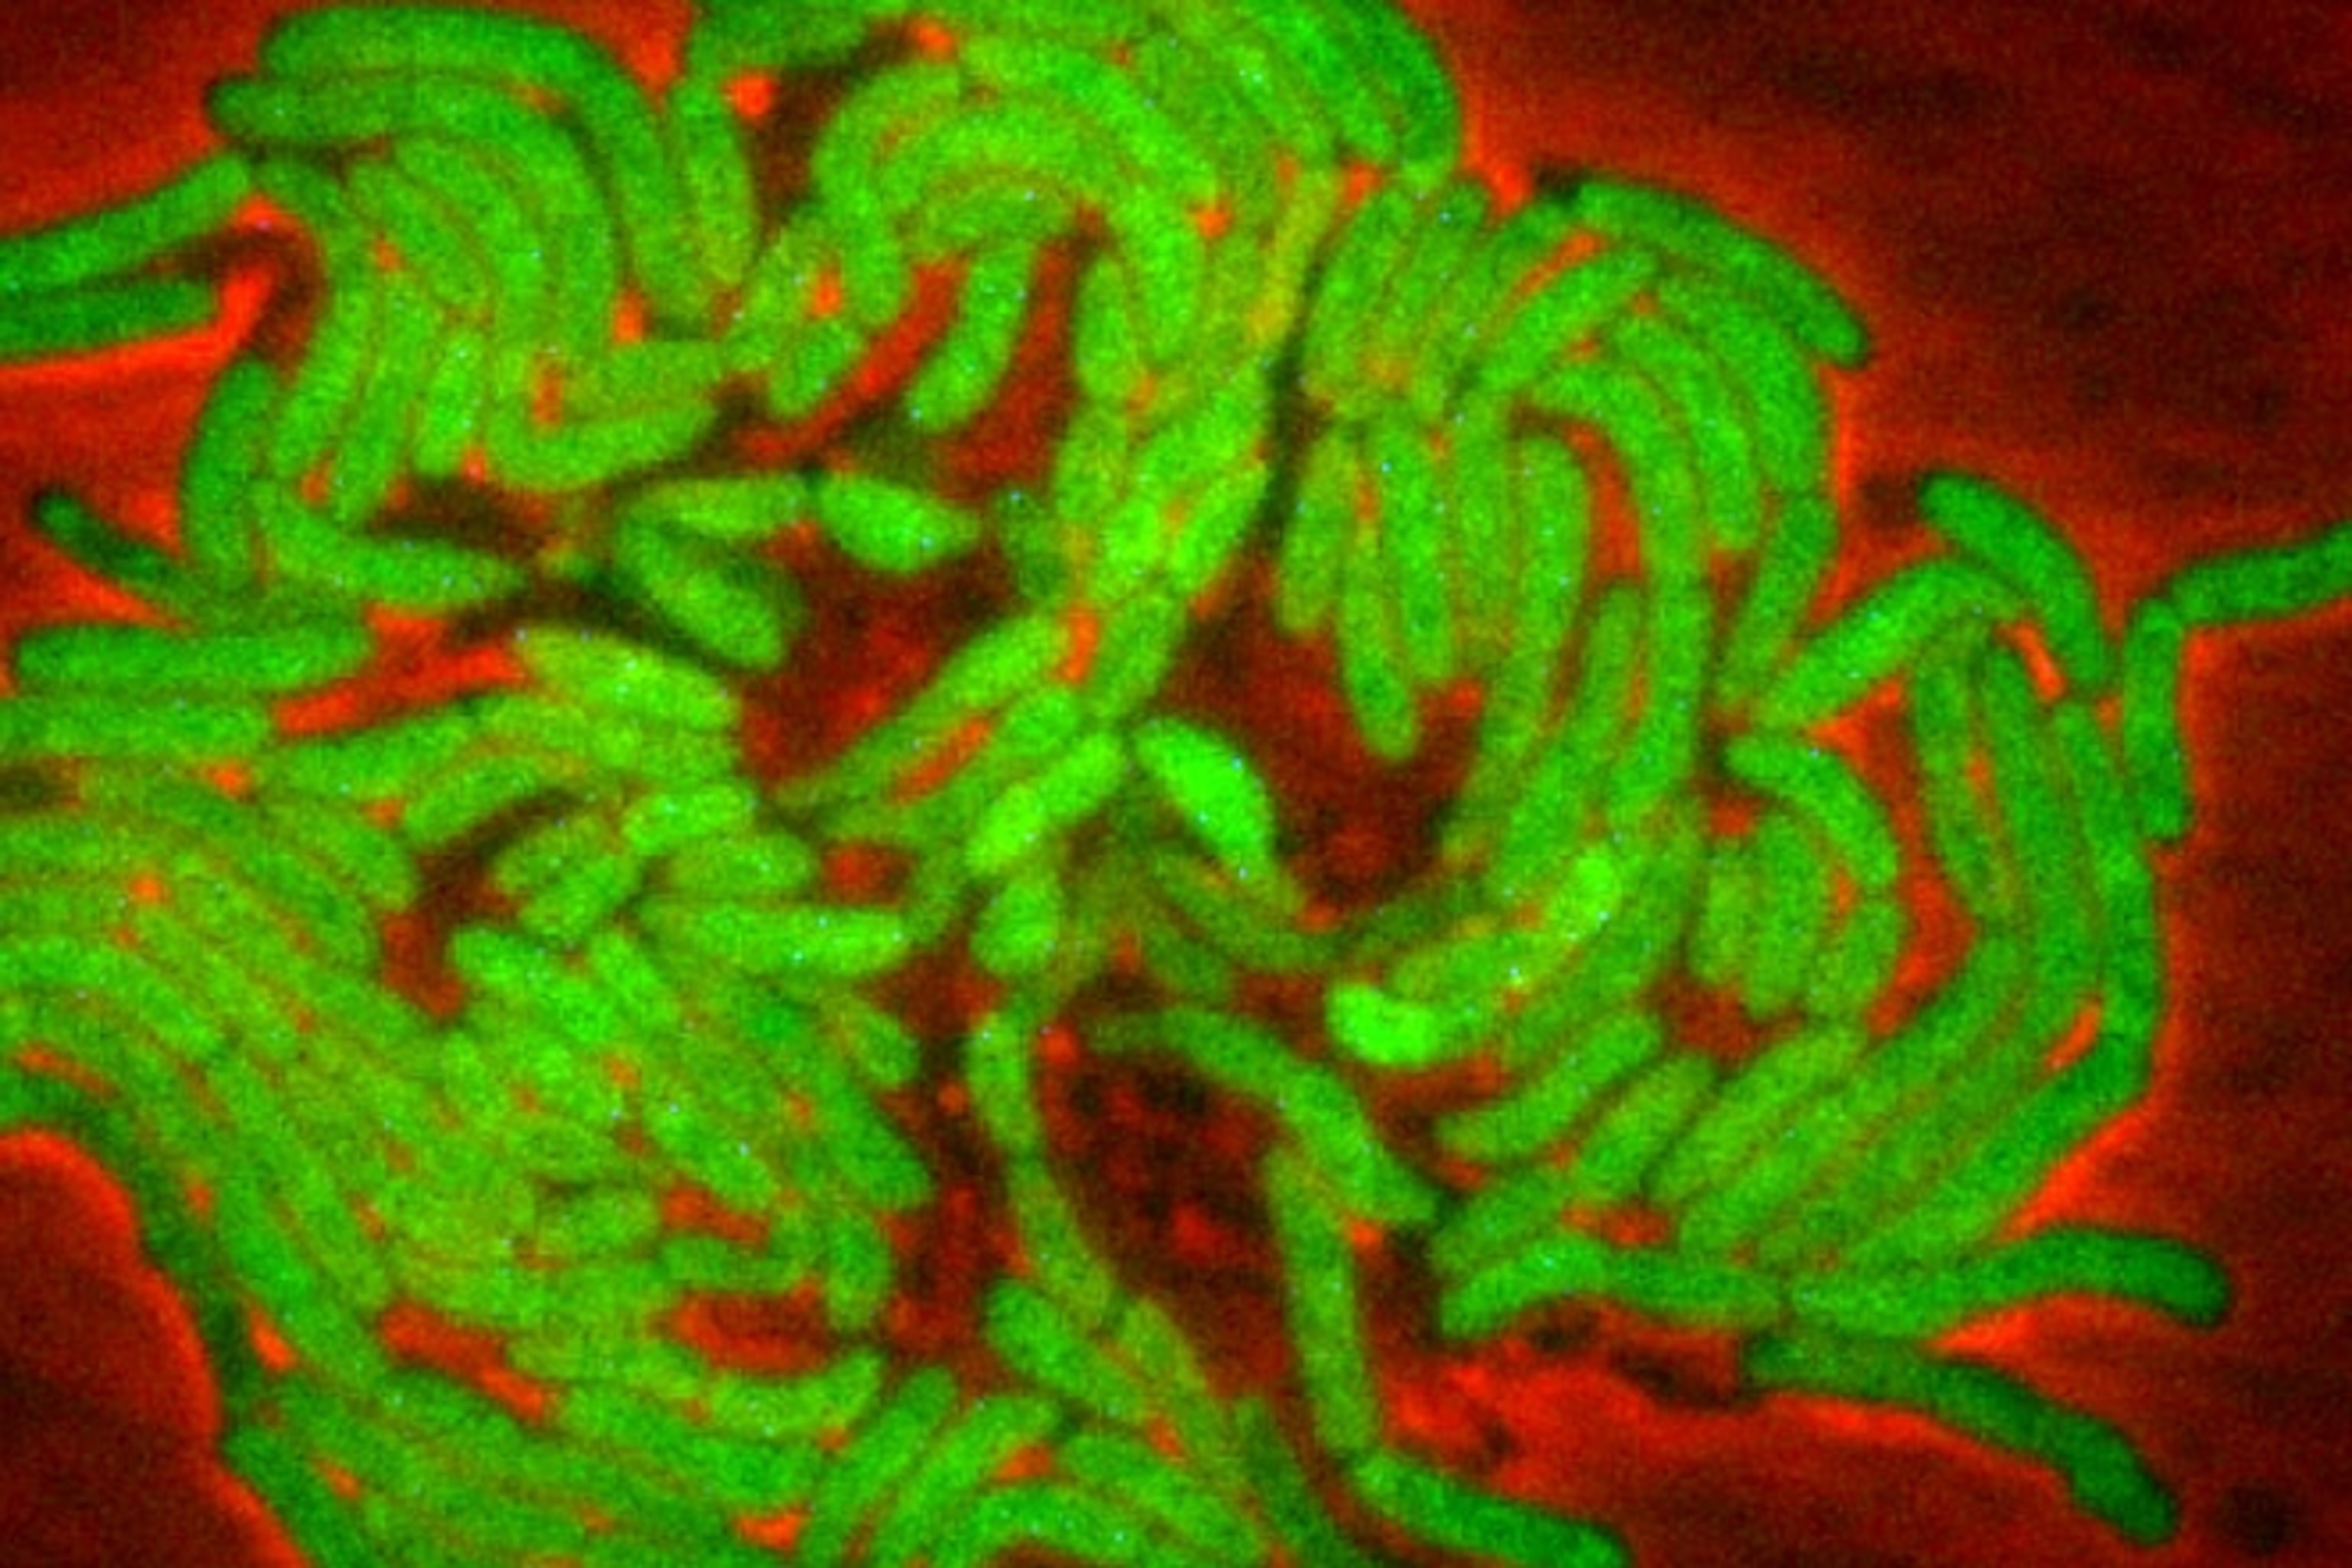

But even this story is too simple. Yuichi Wakamoto and Neeraj Dhar from the Swiss Federal Institute of Technology have questioned the longstanding assumption that persisters don’t grow, or grow very slowly. By studying Mycobacterium smegmatis, a relative of the bug that causes tuberculosis, they found the opposite: Persisters do grow, but they die at an equal rate, creating the illusion of a static population.

Wakamoto and Dhar’s ace card was a technique called microfluidics, which channels microbes along tiny pathways and allows scientists to track them individually. Rather than counting a swirling mass of bacteria growing (or not) in a flask, Wakamoto and Dhar could follow the fate of each cell—an indispensable technique for working out what they’re actually doing.

The duo exposed their microbes to isoniazid, an anti-tuberculosis drug that stops bacteria from building their outer walls. Isoniazid killed off almost 90 percent of the bacteria. The rest were persisters, but contrary to expectations, these survivors kept on growing through the drug assault. And slow-growing cells were just as likely to persist as fast-growing ones.